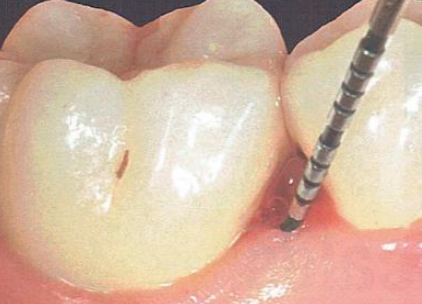

La mise en évidence clinique d’un défaut osseux repose essentiellement sur le sondage parodontal. Cette technique doit être rigoureuse et reproductible :

L’insertion verticale de la sonde parodontale graduée (sonde de Williams ou sonde UNC 15) permet de déterminer la profondeur de la lésion. La sonde est insérée doucement le long de l’axe dentaire jusqu’à rencontrer une résistance osseuse.

L’insertion horizontale dans le sens vestibulo-lingual permet de définir la largeur du défaut et de déterminer si les corticales sont présentes ou détruites. Une sonde passant facilement en vestibulo-lingual signe la destruction des deux corticales — le cratère osseux.

Limite importante du sondage clinique : la sonde détermine la profondeur et la largeur du défaut, mais ne peut en aucun cas définir les limites exactes de la lésion osseuse, ni le nombre précis de parois résiduelles. L’examen complémentaire est donc indispensable.